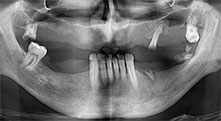

остатъчно съзъбие

40-годишен пациент с много лошо остатъчно съзъбие пожела възстановяване, базирано на импланти. Тъй като е пушач, противопоказен е синус лифт на горна челюст с фиксирана протеза. Планирано е шинирано протезиране върху четири съседни предни импланти.

Piezomed B6

Алвеоларният гребен е разделен на две чрез пиезо хирургия (инструмент: Piezomed B6). Имплантите са поставени наведнъж и периимплантологичната кост е допълнително изградена чрез GBR техника.

Импланти

Четирите импланти са поставени на място, както е планирано. Дисталните молари на горна челюст все още могат да се използват за фиксиране на протезата, която е сложена един месец след имплантиране.